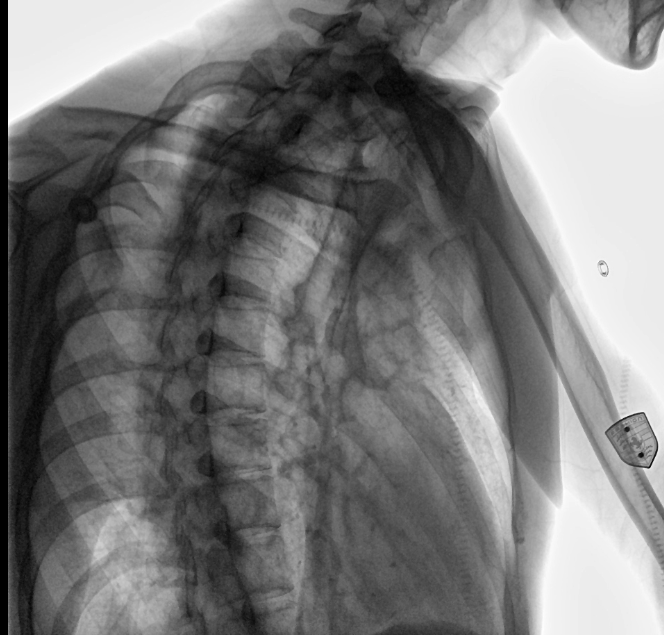

安健科技動(dòng)態(tài)平板DR-DTP571

位于衡水市中醫(yī)醫(yī)院的動(dòng)態(tài)平板數(shù)字化X射線系統(tǒng)DTP571具備高速高清點(diǎn)片功能。這是一款對(duì)放射科十分友好的產(chǎn)品。因?yàn)樗迅咚俸透咔妩c(diǎn)片結(jié)合,既能方便影像技師有效地抓拍需要的病灶的影像,又能給予影像醫(yī)生清晰的影像進(jìn)行診斷。

設(shè)備的穩(wěn)定性,表現(xiàn)性能方面,我院現(xiàn)在這臺(tái)動(dòng)態(tài)DR,一個(gè)上午能夠接待700-800名學(xué)生進(jìn)行體檢工作,如果是使用普通設(shè)備,包含體檢人員脫衣服,擺位置,達(dá)到體檢要求在內(nèi),最快檢查速度是2-3分鐘,但沒有透視功能,無法承載這么多的量,而且需要2位醫(yī)師輪換操作。

動(dòng)態(tài)觀察診斷,實(shí)時(shí)高清點(diǎn)片